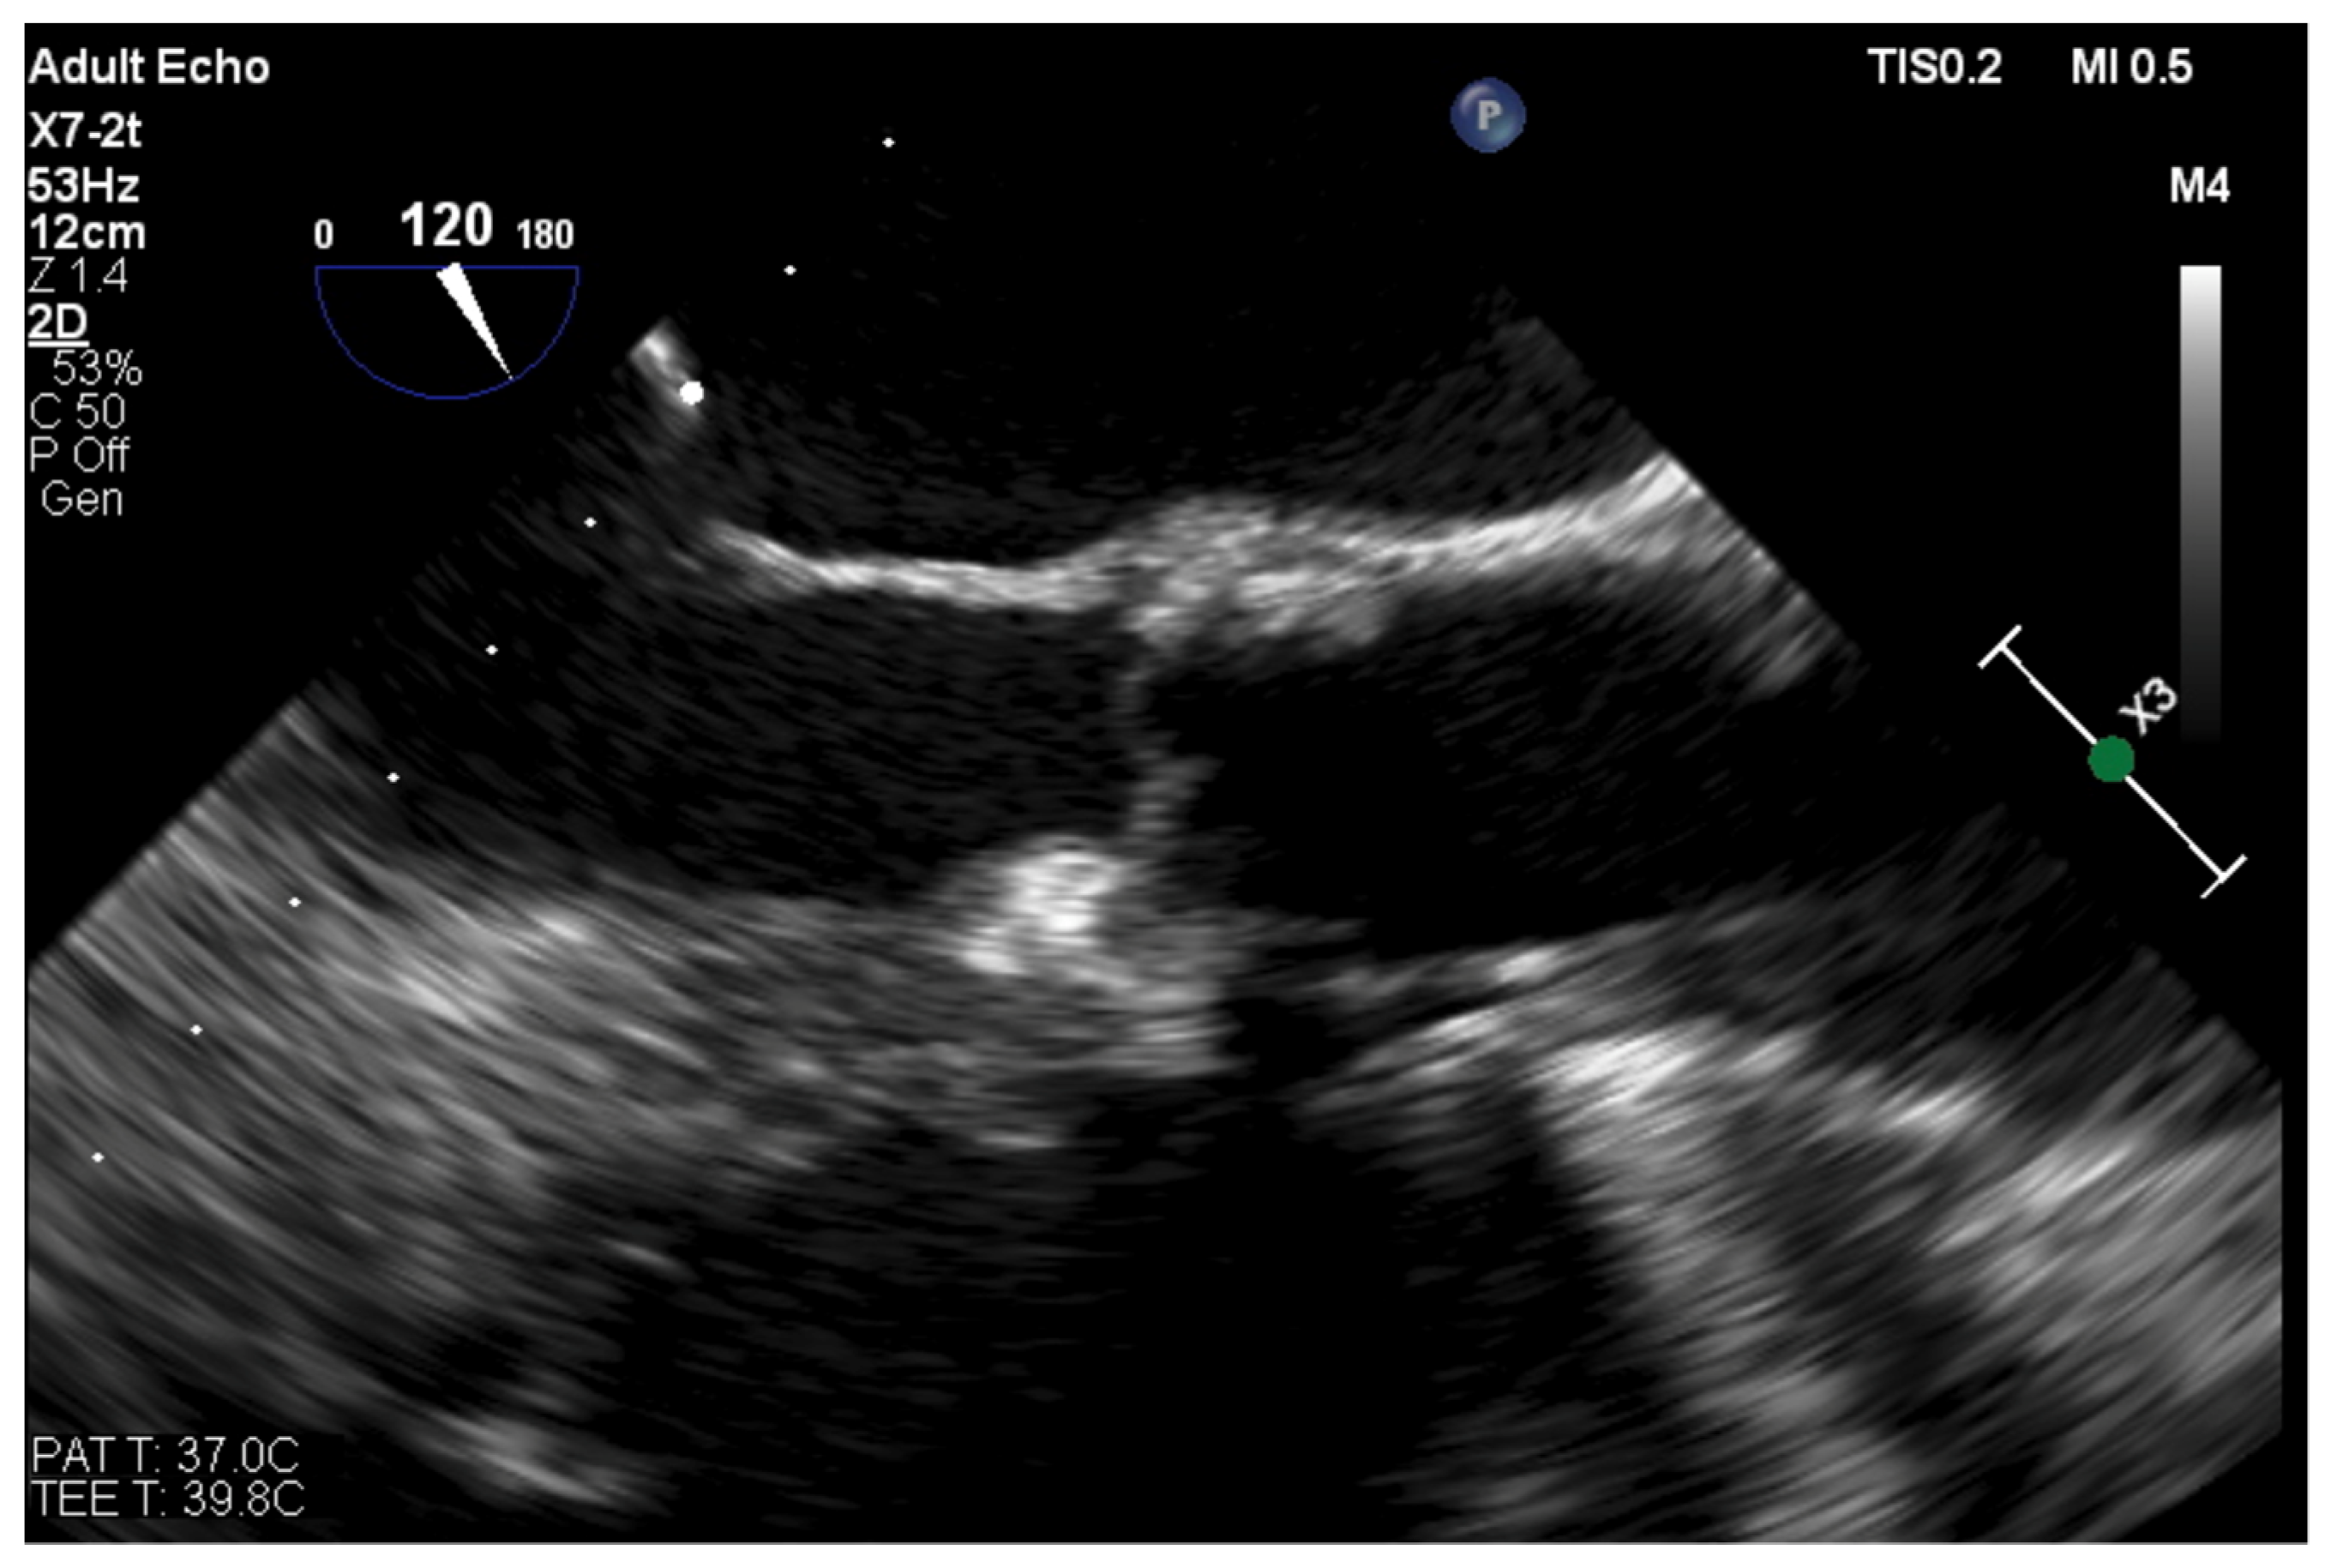

Paravalvular Leak Echo Imaging before and during the Percutaneous Procedure